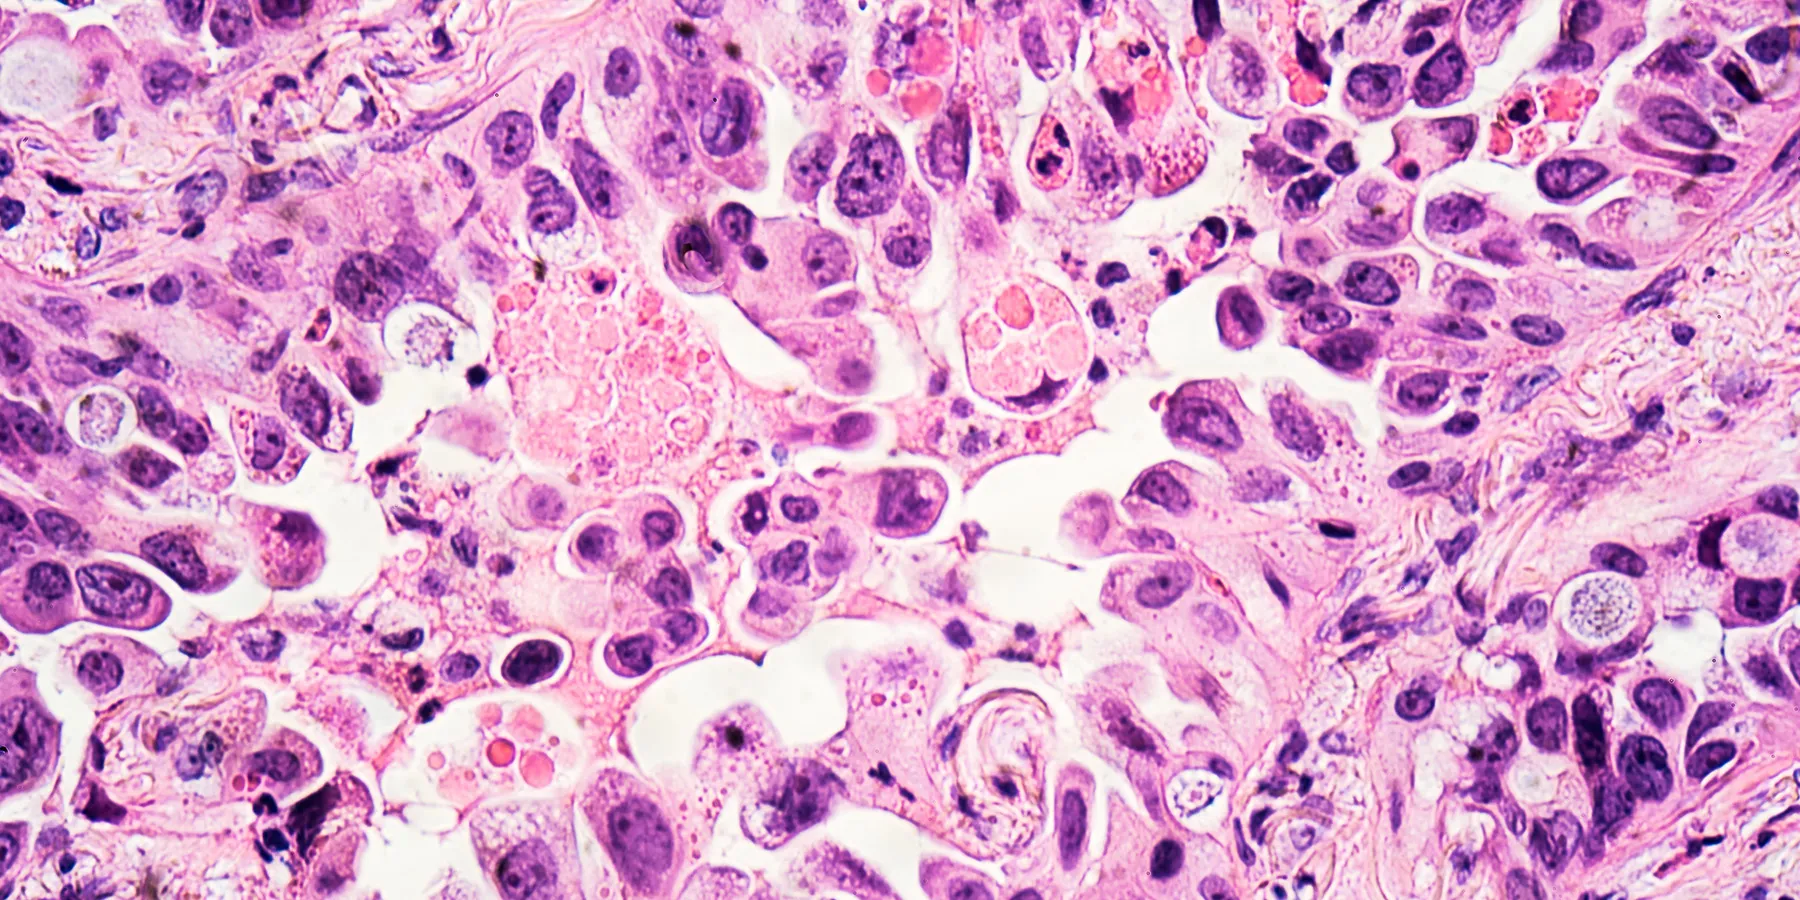

During the study, the multidisciplinary team tested cancer cells’ resistance to chemotherapy and radiotherapy using glioblastoma (GBM) as a test case, because of its plasticity—the ability to adapt to treatment and survive. The findings have been published recently in Science Advances.